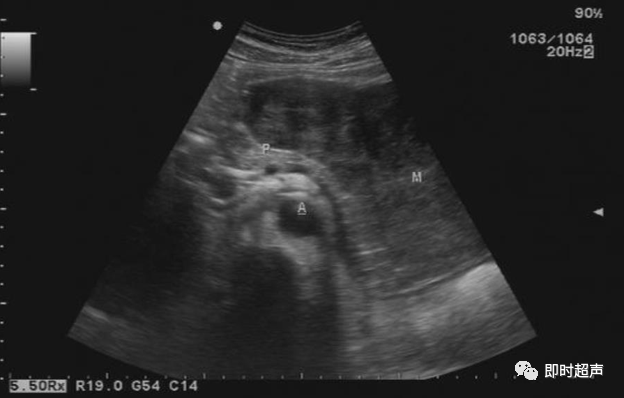

• GIST的发病机制与KIT信号通路的激活有关。• KIT是一种酪胺酸激酶跨膜受体蛋白,未经“装配”过的KIT蛋白是一种非活化的单体,参与细胞膜形成。几乎所有GIST都表达了KIT蛋白,而且大多突变的KIT基因保留了表达KIT蛋白的特性。c-kit内的突变主要见于恶性病例,特别是外显子11的点突变,还有外显子9、13和17,可以导致本质的或配体独立的c-kit激活,引发细胞的无序增殖和凋亡。这些具有功能的突变是GIST发病机理的关键,并且与肿瘤的恶性程度和预后较差相关。• GIST约75%发生于50岁以上老年人,中位年龄为58岁,无明显差异。• 可以发生在消化道从食道到肛门的任何部位,偶尔可原发于网膜、肠系膜和腹膜后,约50%发生在胃,25%发生在小肠,不足10%发生于食管、结肠及直肠。大体观察:肿块多境界清楚,类圆形,结节状,部分有假包膜。切面灰白、灰红,质韧,部分质嫩呈鱼肉状,伴有出血、坏死、囊性变。• 肿瘤组织主要由两种细胞组成,一种为长梭形细胞,细胞质丰富,嗜酸性,细胞核呈梭形或杆状;另一种为上皮样圆形或多角形细胞,细胞肥胖,胞质少。两种瘤细胞常呈束状、编织状或旋涡状排列。• 部分病例细胞异型明显,核分裂象增多,可见病理性核分裂象和瘤巨细胞。梭形细胞界不清楚,胞质丰富,淡染,轻度嗜伊红或略嗜碱,可有纤细、长梭形、短梭形或胖梭形、卵圆形,可见核仁。细胞核两端钝圆,部分病例胞质呈空泡状,位于核一端形成核端空泡胞,多呈交叉束状、旋涡状、席纹状及栅栏状排列。上皮样细胞胞浆丰富或透亮,多呈弥漫片状、束状或巢状排列。肿瘤间质可有出血、囊性变、坏死及黏液变,可见炎性细胞浸润。CD34抗原是一种115kd的糖基化蛋白,50%~80% GIST的CD34表达为阳性,CD34对鉴别GIST和典型的平滑肌瘤,神经鞘瘤还是非常有用的标记物,因后两者的CD34一般是阴性的。但CD34在诊断GIST上其特异性受到限制,一般情况下CD34多与CD117联合应用,方能提高GIST的诊断率。• 与肿瘤大小、发生部位、肿物与肠壁的关系以及肿瘤的良恶性有关。• 肿瘤较小者(直径小于2cm)常无症状,往往在体检和其它手术时无意中发现。• 肿瘤发生于胃肠道腔内时大多表现为呕吐、腹痛及消化道出血,而发生于胃肠道腔外的则主要表现为腹部包块。• 最常见的临床症状是中上腹部不适、腹部肿块及便血。• 对于临床发现的消化道(包括肠系膜、网膜、后腹膜)实体肿瘤,在排除其他常见肿瘤后,才考虑GIST。目前,诊断GIST有三条标准:③肿瘤组织具有梭形细胞和上皮样细胞两种基本细胞成分的病理学特征。这是诊断GIST金标准。CD117阳性者或CD117阴性而CD34阳性者,且伴平滑肌和神经双向分化或无分化者,可诊断为GISTs;以Desmin和SMA强阳性,而CD117阴性诊断为平滑肌肿瘤;以S-100阳性,CD117、Desmin、SMA均阴性诊断为神经鞘瘤。• GISTs的分型与组织学良恶性的关系:研究证实GISTs非单一分化的肿瘤,具有多向分化。• 当前GISTs的良性、交界性和恶性判断标准多参照Amin等提出的标准:②交界性:核分裂<5/50HPF,但肿瘤>5cm;• 另外研究显示,平滑肌型大多数为良性,少数为交界性和恶性,神经源型为恶性,双向分化亚型和未分化型为交界性和恶性,提示GISTs的分化型与其良恶性之间有一定关系。• 胃间质瘤早期多局部侵犯,后期出现肝转移和腹腔内种植,小肠间质瘤早期即可出现转移• 主要有超声扫描(检出率30%左右)、纤维内镜、超声内镜、CT、MRI、普通X• 线检查(胃肠钡餐造影、小肠插管气钡双重造影)、选择性血管造影检查等。• 不同部位的GIST,各种检查方法的敏感性不同。以CT检查为佳,尤其是螺旋CT,分辨率最高,可以三维重建,直接显示肿瘤大小、形态、密度、内部结构、边界,对邻近组织的侵犯也看得很清楚,同时还可观察其他部位的转移灶,有利于分期、鉴别与诊断。• MRI具有多轴成像及反映肿瘤内部成分的优点,尤其是动态扫描及各种新的扫描系列的出现更使其可以普及应用。• DSA检查对于GIST,特别是有消化道出血的患者更有价值。• 上述影像学检查表现并非特异性,与胃肠道平滑肌肿瘤、神经源性肿瘤鉴别困难。明确诊断要依赖病理免疫组化等手段。• 超声图像特征 肿物体积较小者(直径< 5. 0 cm )多为实性病变, 呈类圆形, 边界清晰, 内部回声多为较均匀的低回声。• 肿物体积较大者(直径> 5. 0 cm ) 多为混合性病变,呈不规则圆形或分叶状, 多数边界尚清晰, 以实性为主的病变内部为不均质中低回声伴不规则液性区及斑点状强回声; 以囊性为主的病变囊壁较厚,有分隔, 部分囊腔内可见点状、团状低回声。CDFI显示肿物实质回声内血流均较丰富。病例1:患者男, 62岁。自扪腹部包块2月余,包块增大20天就诊。查体:腹部平坦,无腹壁静脉曲张,无胃肠型及蠕动波,腹肌软,剑突下5cm处及左肋缘下可触及一质韧包块,大小约15*12cm,活动度差,边界尚清,包块深压痛,全腹无反跳痛。化验检查AFP:3.66(1.09-8.04)ng/ml,CEA:2.85(0-5)ng/ml。体格检查:一般情况良好,全腹软、平坦,腹部无压痛。超声检查:患者仰卧位时左上腹于胰尾前方可见一大小约6. 1 cm ×5. 8 cm ×5. 3 cm实性均质低回声,形态规则,包膜完整,边界清晰,活动度大;右侧卧时,肿块移至胰头右前方(图1) ;于其内探及丰富血流信号。体格检查:一般情况良好,腹丰满,上腹部有轻压痛,未扪及明显肿块。超声检查:患者仰卧位时左上腹于胰尾前方、脾门处可见一大小约10. 0 cm×8. 8 cm×7. 6 cm 实性低回声(图2) ,形态规则,包膜完整,边界清晰,肿块活动度大;右侧卧时,肿块移至左肝下间隙,回声尚均质;于其内探及较丰富血流信号(图3) 。图3 腹腔低回声肿块位于左肝下间隙,于低回声肿块内探及较丰富血流信号向壁外生长的胃肠道间质瘤, st为胃腔,箭头所指为胃壁, T为向外生的肿瘤• 胃间质瘤的定位准确率要高于十二指肠及小肠间质瘤,这主要是因为胃的解剖位置相对固定,且通过饮水使胃腔充盈,可清晰的显示胃壁的各层结构及肿块与胃壁的关系。肿块多表现为粘膜下、肌层或浆膜下低至中等回声团块,可向腔内、腔外或腔内外生长。但当肿瘤较大或浸润周围脏器时,超声定位仍有困难, 因此,超声如发现上腹部肿块且怀疑来源于胃者,应尽可能嘱其饮水充盈胃腔,并多角度、多切面观察肿块与周围脏器的关系,以提高定位的准确性。• 十二指肠间质瘤的定位亦较准确,但降部的外生性肿块常与胰头粘连而误诊为胰腺肿瘤回声均匀且位置较深的间质瘤亦可能误为胰头周围淋巴结。• 空、回肠间质瘤常因肿块较大,多发,位置不固定而难以定位,往往误诊为腹、盆腔或腹膜后肿瘤,超声检查如发现肿块局部肠壁增厚,肿块与肠道随呼吸同步运动时可作出定位诊断。• GIST的声像图表现有助于其良、恶性的鉴别:良性肿瘤多体积较小,圆形或椭圆形,回声均匀,边界清晰。恶性肿瘤多较大,呈不规则分叶状,回声不均匀,内部易出血、坏死、囊变。• 肿瘤长径与肿瘤内部是否出现无回声区在良、恶性病变之间的差异有统计学意义,是判断良恶性的有效征象。• 如以肿瘤长径>5cm为诊断恶性标准,其敏感性、特异性及准确性均较理想。超声可为临床提供胃肠道间质瘤的部位、大小、边界、回声等较多有用信息,一部分病例可作出定位、定性诊断,并可在术后或复发患者药物治疗期间对其进行动态观察;CDFI方便快捷、无需造影剂即可对间质瘤周边及内部血流进行观察,可为临床医师提供肿瘤血供情况。但未发现腹腔或肝脏转移时,超声判断胃肠道间质瘤性质有一定难度。• 目前临床上对GISTs的治疗效果并不十分满意。治疗仍以手术为主,对无法手术切除或已有转移的GISTs患者进行甲磺酸伊马替尼化疗。• 手术方式取决于肿瘤大小、部位和术中冰冻切片结果等。• 发生在胃的间质瘤,可首选胃大部切除术;发生在十二指肠的间质瘤可行保留胰头的十二指肠切除术或胰十二指肠切除术;发生在小肠的间质瘤可行肿瘤肠段切除术;发生于结肠的间质瘤可行左半或右半结肠切除术;发生于直肠的间质瘤可行肿瘤局部切除术。一般情况下无需淋巴结清扫。• 术后随访监测,复发者单个病灶可考虑手术切除;多发或转移特征者应试行甲磺酸伊马替尼化疗,并监测肿瘤大小及数目的改变。• 随着分子靶点药物进入肿瘤临床,一种小分子化合物———酪胺酸激酶受体抑制剂,美国称为Gleevec,欧洲叫做Glivec(格列卫),在治疗GIST和慢性粒细胞白血病方面有其独特的作用。已知细胞膜表面上皮生长因子受体酪胺酸激酶抑制剂大致分为两大类:一类是小分子化合物;另一类是特异性抗体。利用抑制酪胺酸激酶的活性,对处于增殖期状态的病变具有治疗的作用。Glivec在体外、体内和细胞水平都可强烈抑制酪胺酸激酶的活性,是干细胞因子(SDCF)受体KIT的强抑制剂。• Glivec推荐用量为400mg(4片),每日一次, 3个月为一疗程。如服3个月后无效可加至600mg/d~800mg/d(6~8片)[18];若仍无效果不再增量应停止治疗。• Glivec治疗进展转移的GIST总有效率为50%左右,比传统化疗有效率高十倍以上;肿瘤生长控制率达80%以上,起效最快在服药后24h之内,使症状改善如疼痛缓解;平均起效时间为13周(约3个月)。患者体力状况改善是又一突出效果。2/3患者治疗后无症状可如健康人生活工作。• Brainard等研究发现间质瘤预后差的前两位因素为肿瘤大小和核分裂象,故对于间质瘤直径>5cm和核分裂象>5/50HPF的患者应给予口服Glivec。最近,Liu报道口服Glivec治疗可使85%患者的病情得到控制。